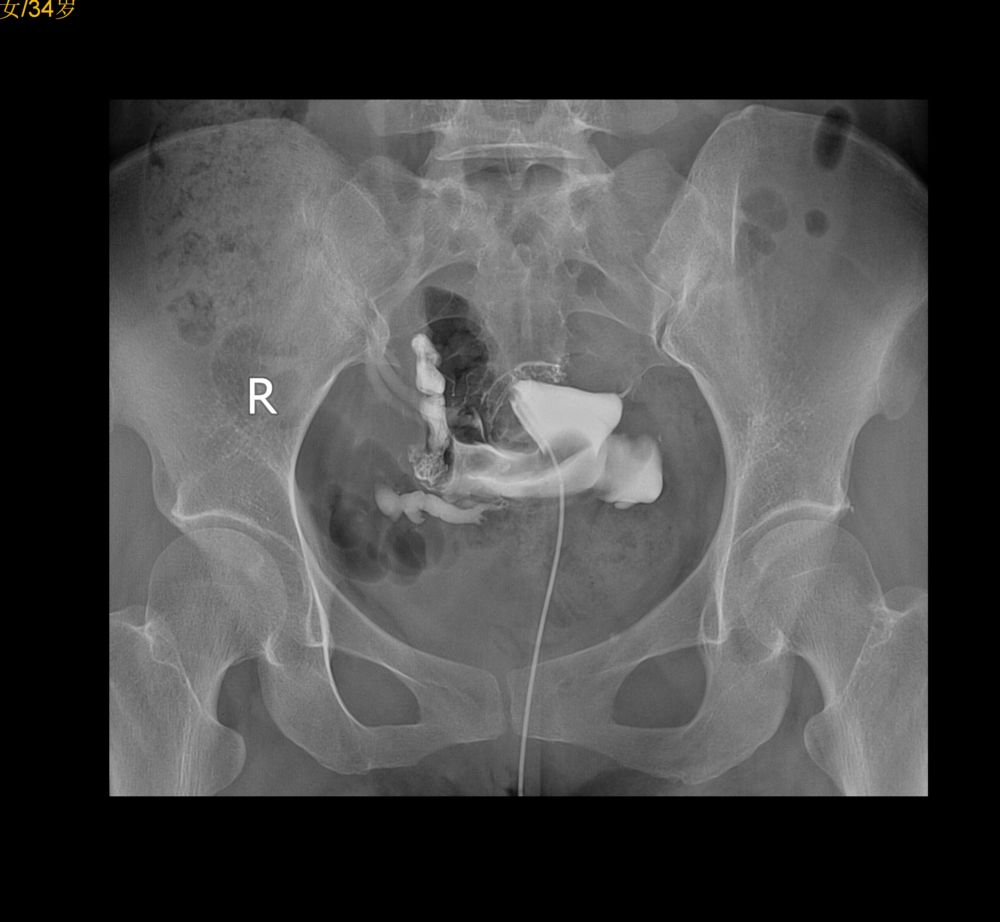

右侧输卵管通,壶腹部粗细不均,右侧宫旁静脉回流,左侧峡部不通,不是是否结扎吻合术后?

左侧输卵管峡部梗阻;右侧宫旁静脉回流。

左侧输卵管不通,右侧输卵管壶腹部粗细不均。

左侧输卵管角部梗阻,右侧宫旁静脉回流

子宫腔规整,右侧输卵管通畅,左侧输卵管阻塞。

左侧输卵管峽部梗阻,右侧宫旁静脉回流。